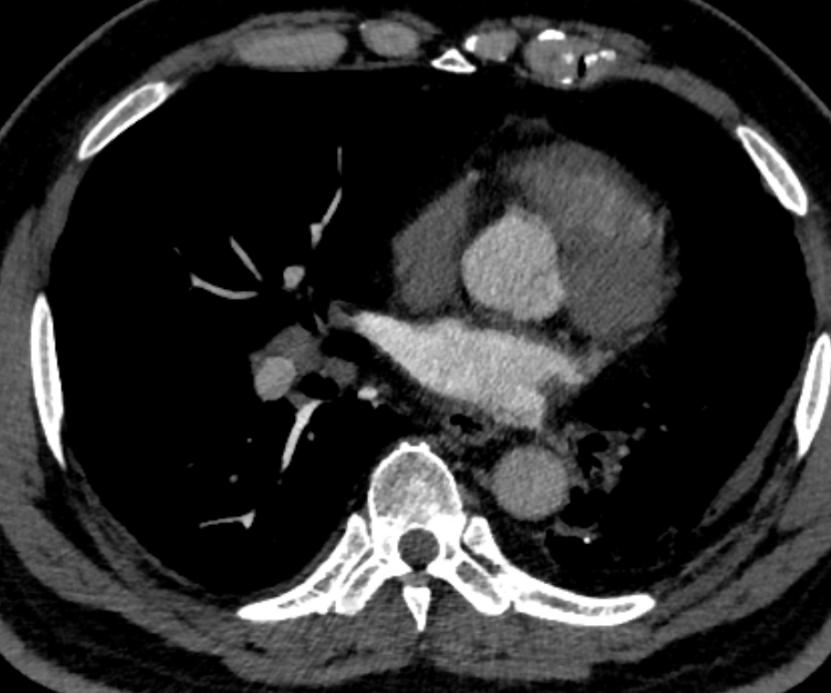

灌注不足 主动脉弓CT值过低

在应用间接法-智能追踪扫描方式时,如果留置针位置选择不当,可能会出现大部分对比剂未能第一时间参与灌注,导致在肺循环中对比剂与血液比例远低于正常值,即便达到靶血管的阈值,而感兴趣区CT值仍然过低,影响诊断。